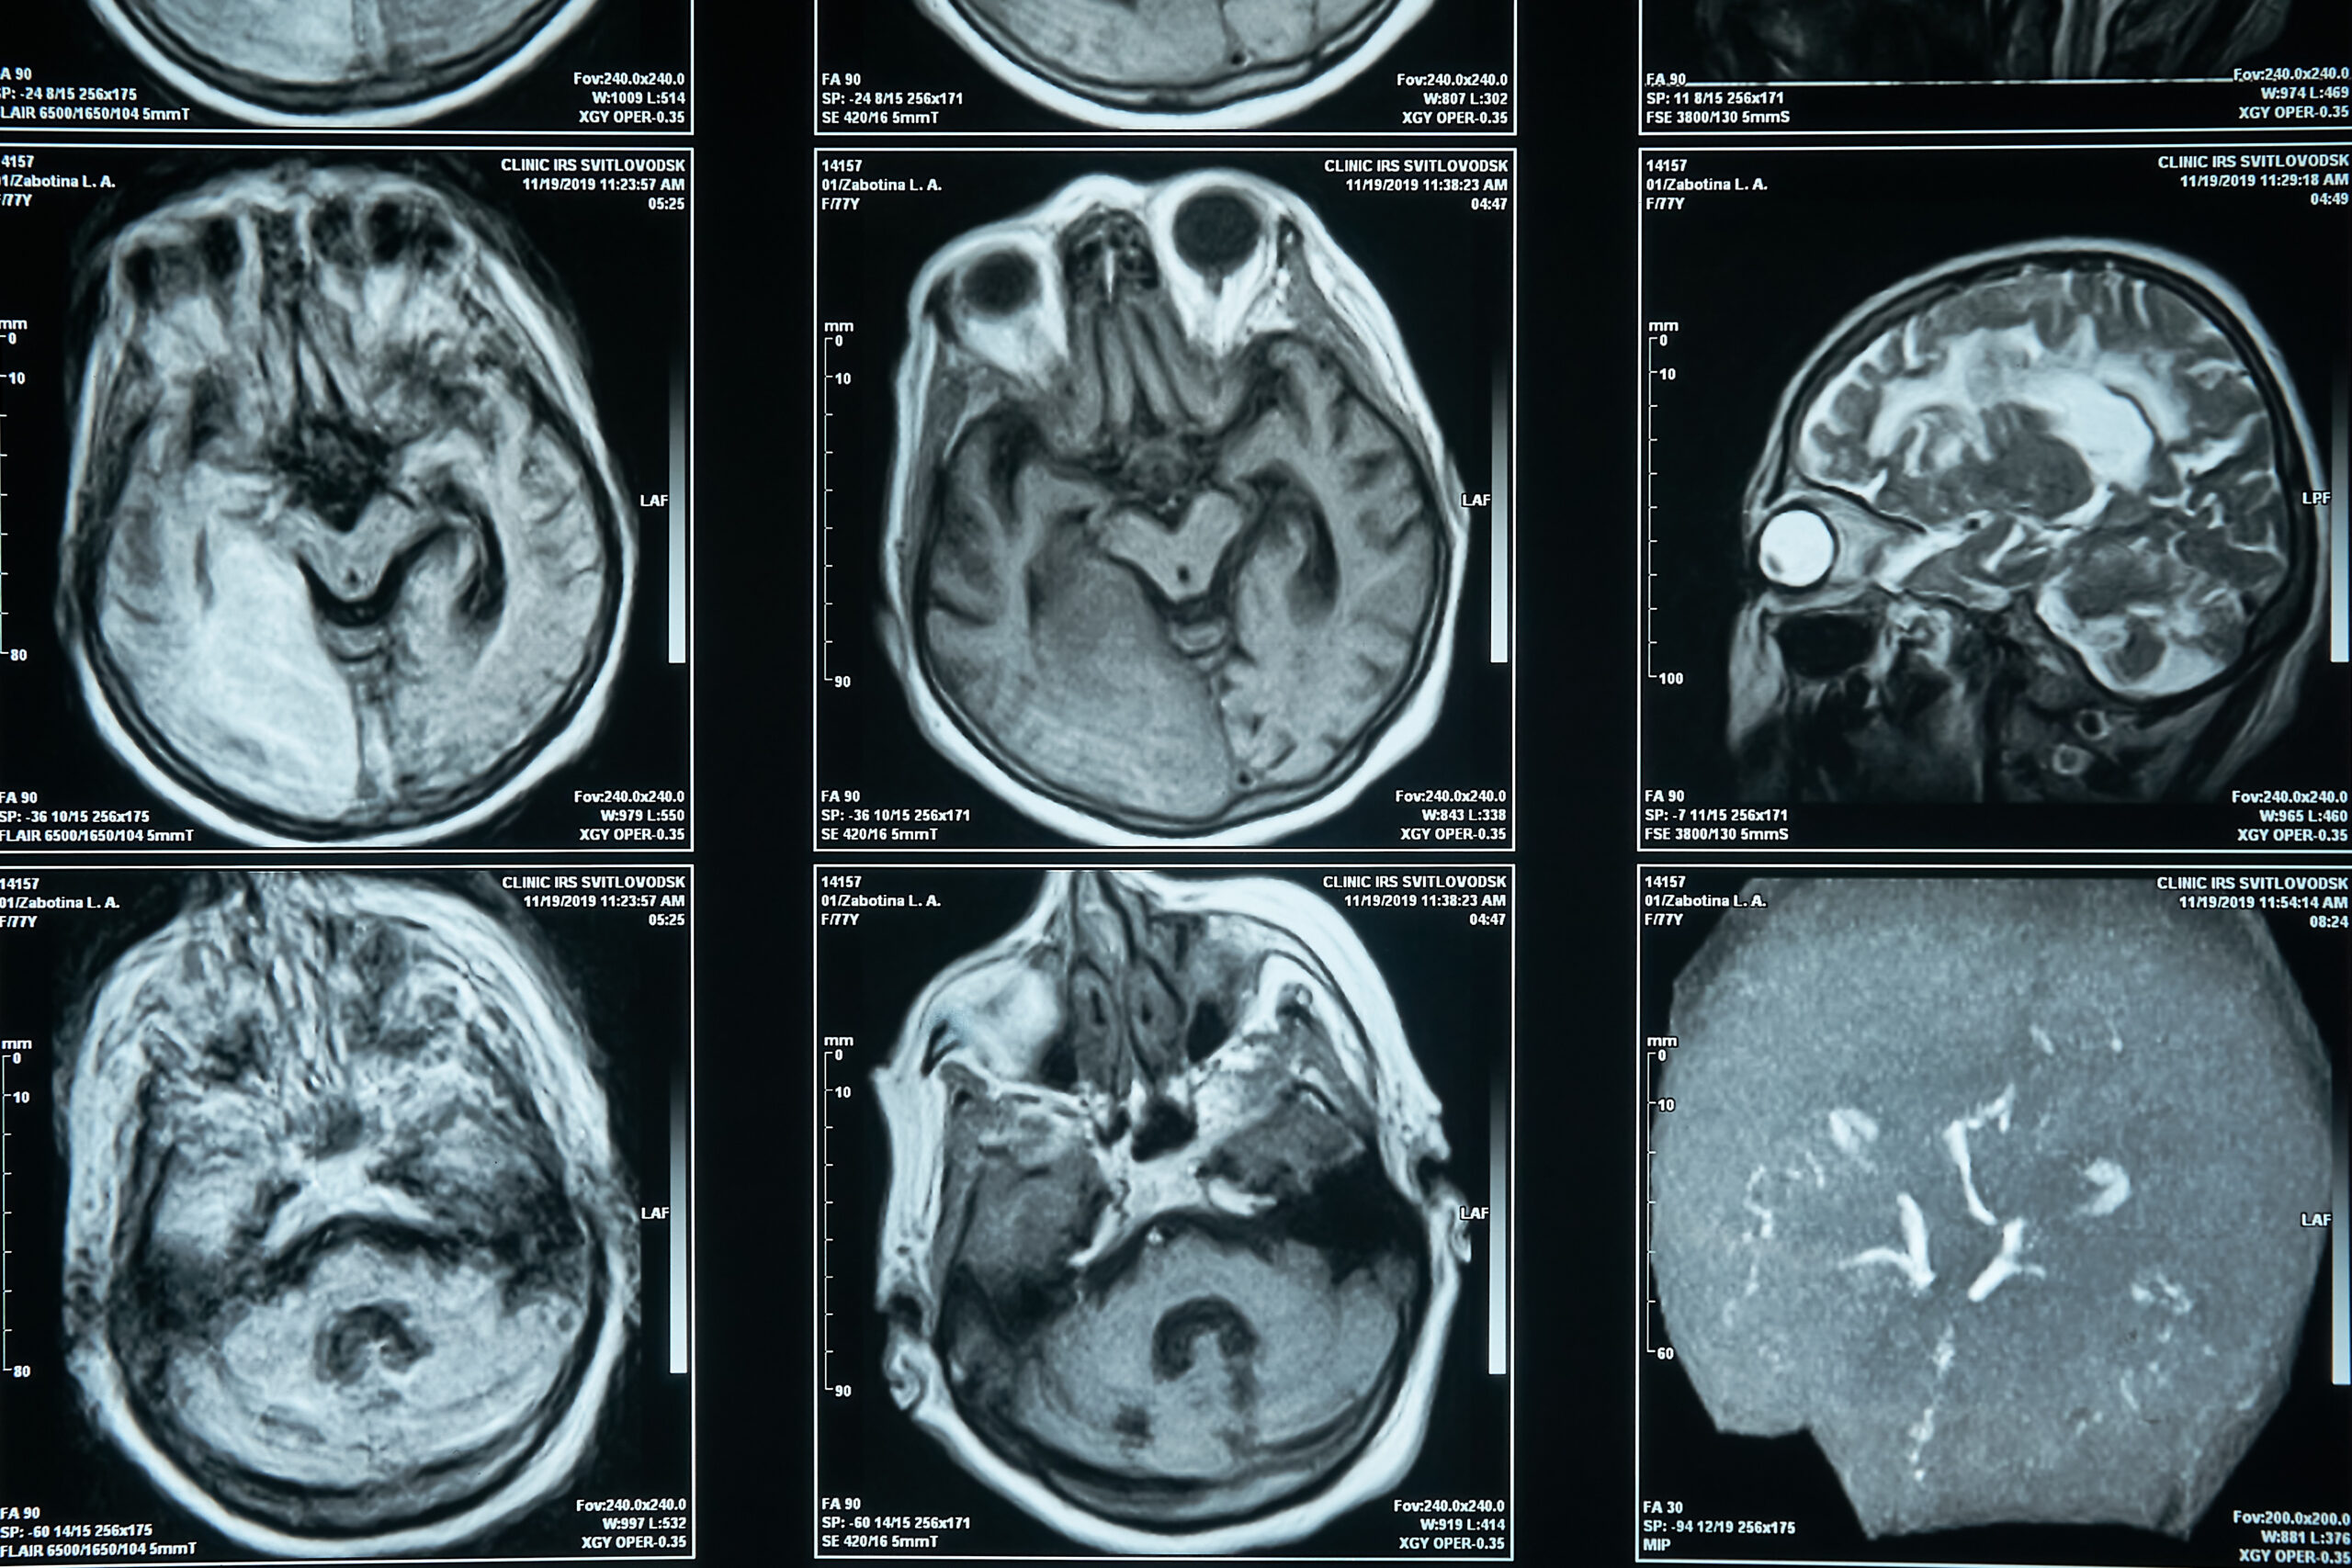

Brain MRI (epilepsy protocol) to look for structural causes